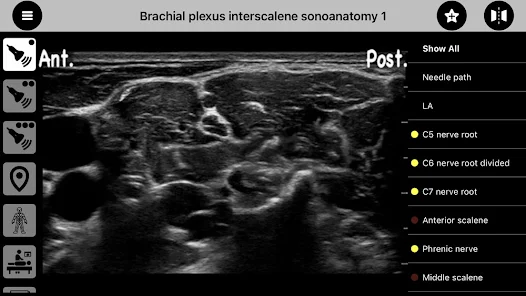

"AnSo Anaesthesia Sonoanatomy" es una innovadora aplicación móvil diseñada específicamente para profesionales de la anestesiología y la medicina. Esta herramienta se centra en proporcionar una comprensión profunda de la anatomía sonográfica, facilitando el aprendizaje y la práctica de técnicas de anestesia regional. Con una interfaz intuitiva y recursos educativos de alta calidad, "AnSo" se convierte en un aliado indispensable para anestesistas, residentes y estudiantes de medicina.

• Imágenes de alta resolución: La aplicación ofrece imágenes sonográficas de alta calidad que permiten a los usuarios visualizar la anatomía de manera clara y detallada.

• Guías interactivas: Incluye guías paso a paso para realizar bloqueos nerviosos y otros procedimientos anestésicos, lo que facilita el aprendizaje práctico.